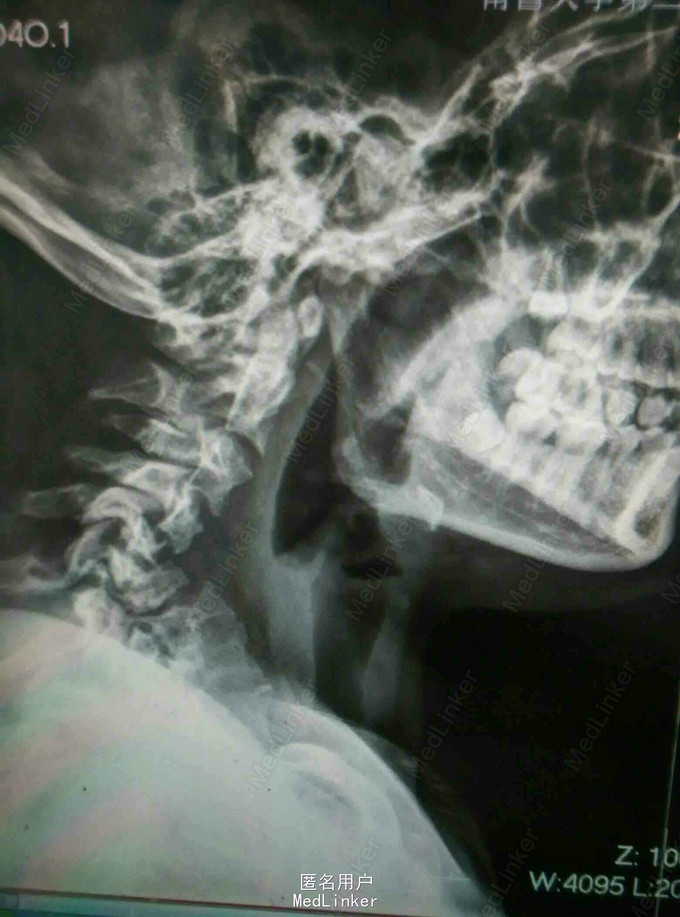

颈肩痛伴左侧肢体无力5月 患者青年男性,无明显诱因出现颈肩痛,性质钝痛,伴有左侧肢体无力,症状反复发作五月。于当地医院就诊查核磁提示颈椎结核,椎旁脓肿。患者二便正常,既往结核病史。

查体:颈椎生理弯曲消失,各棘突及椎旁压痛,胸腰椎生理弯曲不在,各棘突无压痛,椎旁无叩击痛。左侧肢体肌力降低,双侧Hoffoman征阳性,Babinski征阳性。 辅查:我院磁共振提示颈椎结核并椎旁脓肿,颈椎失稳。

诊断:颈椎结核伴椎旁脓肿 颈椎不稳 四肢不全瘫。 治疗:颈前路病灶清除植骨融合内固定术+Halos架固定,术后护肝抗结核治疗